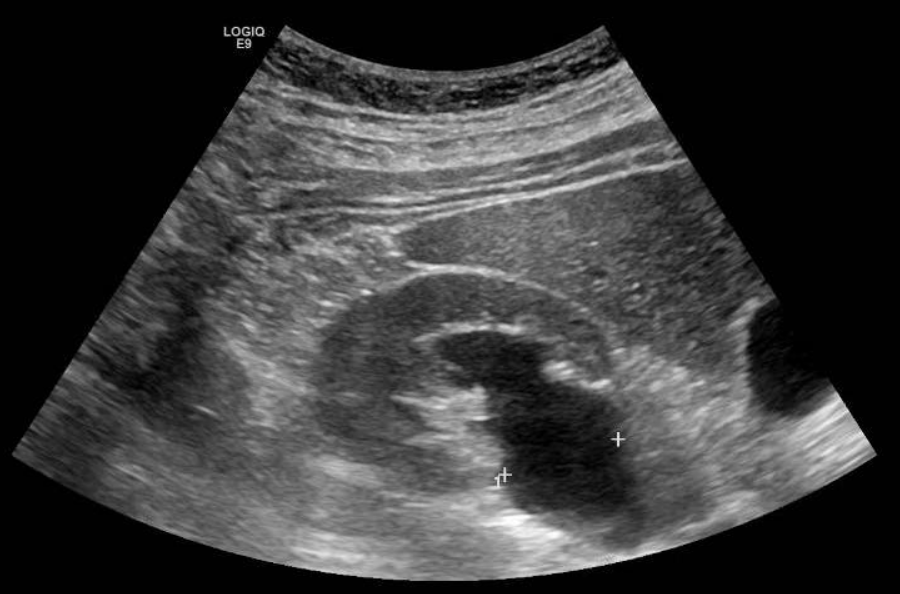

Se solicita ecografía abdominal donde se observa el riñón derecho de tamaño normal, con adelgazamiento parenquimatoso difuso secundario a ureterohidronefrosis severa que se extiende hasta la unión vesicoureteral, donde se visualiza una lesión anecoica intravesical, en relación con el ureterocele ya conocido, que condiciona el cuadro obstructivo.

Se deriva a consultas de Urología. Se completa estudio con uro-TAC que muestra hallazgos similares y gammagrafía renal que sugiere obstrucción parcial del sistema excretor renal derecho a nivel de la unión vesicoureteral con función relativa del riñón derecho del 43% y riñón izquierdo del 57%.